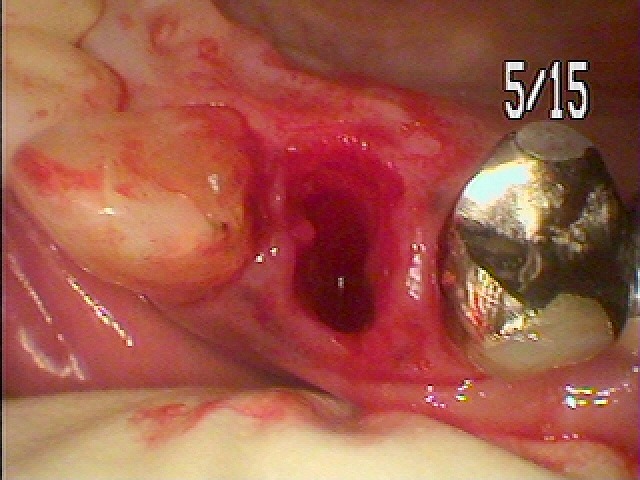

右上の4番部になります

近心部に穴が開いていました

抜歯を行っていきました